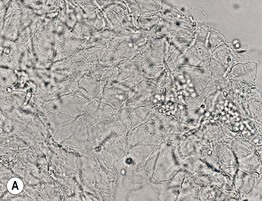

• Microscopic examination of scale (stratum corneum), obtained via scraping with a metal blade or glass slide and mounted in KOH, is commonly performed to confirm superficial cutaneous fungal infections (Fig. 2.1).

Fig. 2.1 Microscopic examination of potassium hydroxide (KOH) preparations of scale. A Tinea (pityriasis) versicolor due to Malassezia spp. with short mycelial forms and clusters of yeast forms. B Tinea corporis due to a dermatophyte with hyphae that cross over more than one cell (squame) and are branching. Chorazol black has been added to the KOH and the stained hyphae are easier to detect. C Branching mosaic pattern that represents the junctures of normal epidermal cells; this is a cause of false-positive KOH exams. D Cutaneous candidiasis with yeast forms and pseudohyphae. Pseudohyphae can sometimes be difficult to distinguish from hyphae. A, Courtesy, Ronald Rapini, MD; C, Courtesy, Louis Fragola, MD; D, Courtesy, Frank Samarin, MD.

• These fungal infections include tinea (pityriasis) versicolor, tinea corporis/faciei/manuum/cruris/pedis, and cutaneous candidiasis (see Chapter 64 on fungal diseases).

• Addition of chlorazol black to the KOH can improve detection (see Fig. 2.1B).

• Neither the genus nor the species of a dermatophyte can be determined by the KOH examination of scale.